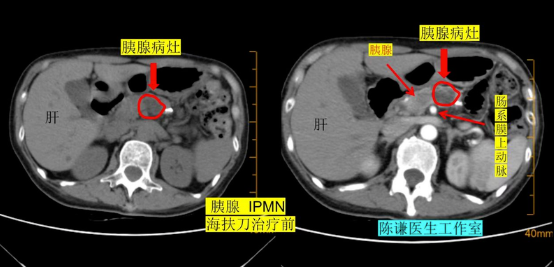

72 岁的北京张先生(化名)从未想过,一次常规体检会让他陷入两难。检查报告显示:胰腺发现占位性病变,高度怀疑为胰腺导管内乳头状黏液瘤(IPMN) 。这个陌生的医学名词让他一头雾水 —— 既没有腹痛、腹胀,也没有恶心、黄疸等不适,怎么就查出了 “肿瘤”? 其实,IPMN 是一种起源于胰腺导管上皮的肿瘤性病变,以导管扩张、上皮乳头状增生和黏液分泌为特征,虽多为良性或低度恶性,但部分类型存在恶变风险,且随着病灶增大,恶变概率会逐渐升高。张先生的病灶已出现 “逐渐增大” 的趋势,当地医院给出了明确建议:尽快